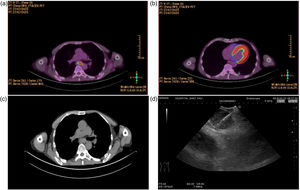

A 57-year-old male ex-smoker, with human immunodeficiency virus (HIV) infection without active treatment by their own decision presented to a hospital because of weakness and weight loss. Blood culture and virus test were negatives and chest X-ray showed no apparent lesions. A cranial CT and lumbar puncture ruled out infection. A positron emission tomography/computed tomography (PET/CT) showed a hypermetabolic pulmonary nodule (14mm, SUVmax 6.76) in left lower low (LLL) and enlarged mediastinal lymphadenopathies (subcarinal 25mm, SUVmax 19.03) (Fig. 1). EBUS-TBNA (EB-1970UK, Linear-Array; Pentax Medical Company) was performed under general anaesthesia by an anaesthesiologist using intravenous midazolam, propofol and fentanyl. With a 22-gauge needle (ECHO-HD-22-EBUS-O, Cook Medical Company), we performed two punctures and obtained cytological samples and cell blocks, evaluated by rapid on-site evaluation (ROSE). Then procedure with 22-gauge histological needle (ECHO-HD-22-EBUS-O-C), and after two punctures, a cryoEBUS was performed in subcarinal region, introducing a 1.1mm cryo-probe (Erbecryo 20402-401, Tubingen, Germany), obtaining three cryobiopsies (Fig. 1). The procedure was well tolerated and no complications were observed, nor 72h later. Cytological studies showed lymphocytes without malignant cells from either the punctures or the cell block. The cultures did not show germs, and the polymerase chain reaction (PCR) and mycobacteria's culture were negatives. Finally, in cryoEBUS culture grows M. branderi and patient was referred to infectious unit for assessment.